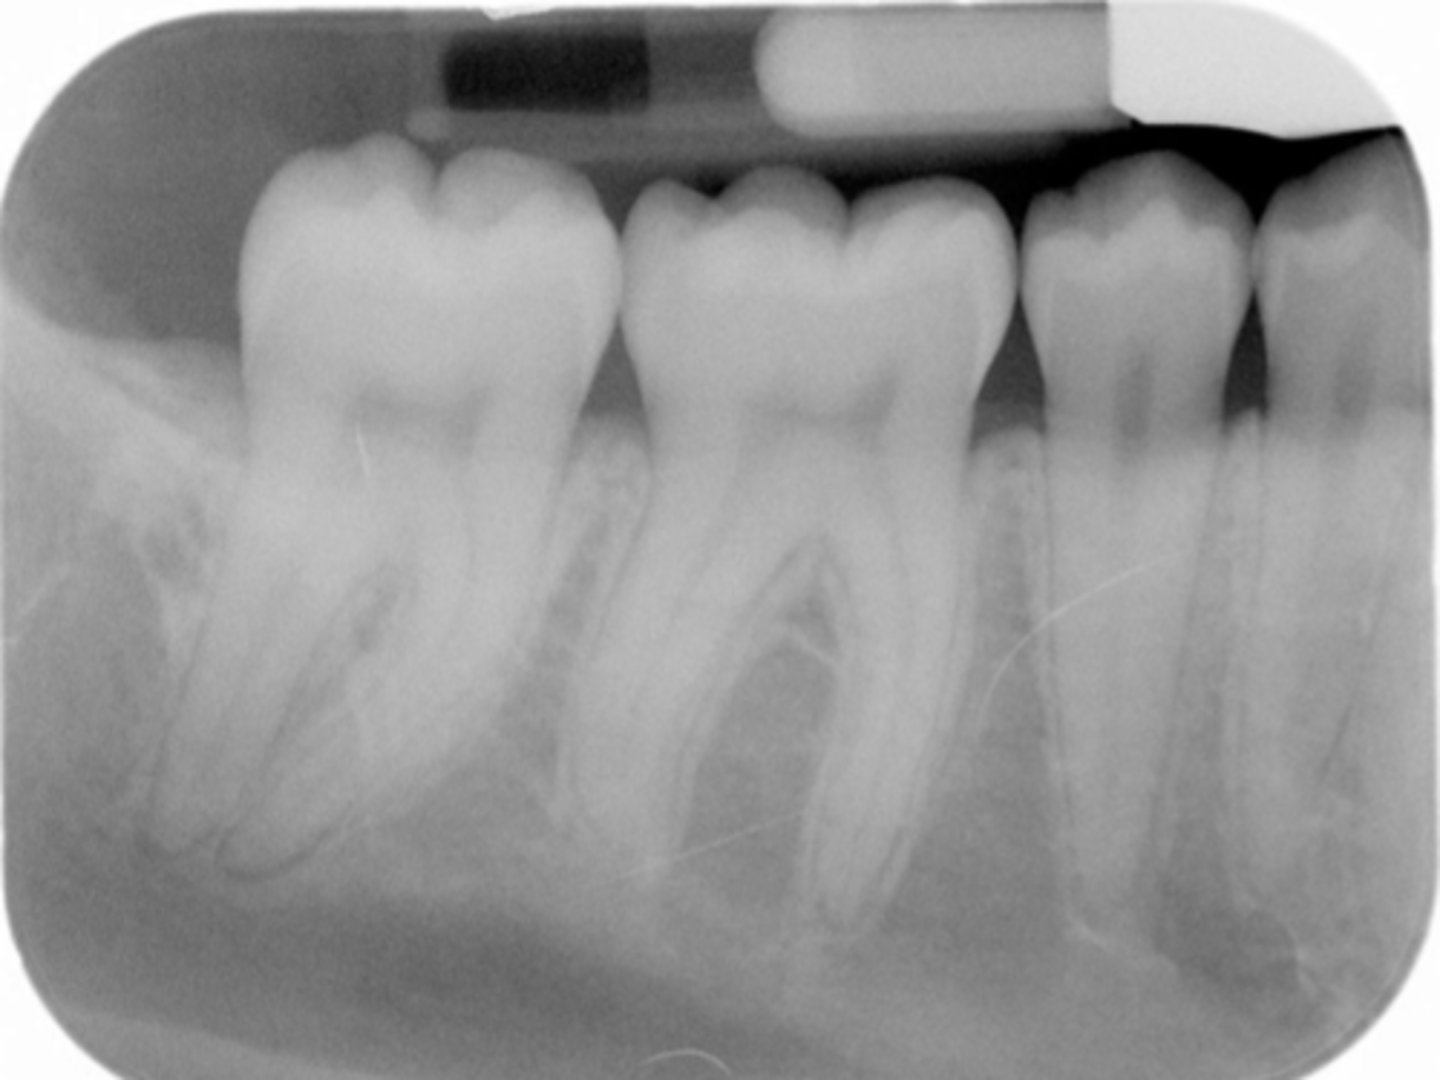

Underexposed Receptor

Receptor

May occur with digital sensors or film

Appearance

The image appears light or low in density.

Cause

The receptor was underexposed.

Correction

Check the exposure time, kilovoltage, and milliamperage settings on the x-ray machine before exposing the receptor.

<p>Receptor</p><p>May occur with digital sensors or film</p><p>Appearance</p><p>The image appears light or low in density.</p><p>Cause</p><p>The receptor was underexposed.</p><p>Correction</p><p>Check the exposure time, kilovoltage, and milliamperage settings on the x-ray machine before exposing the receptor.</p>